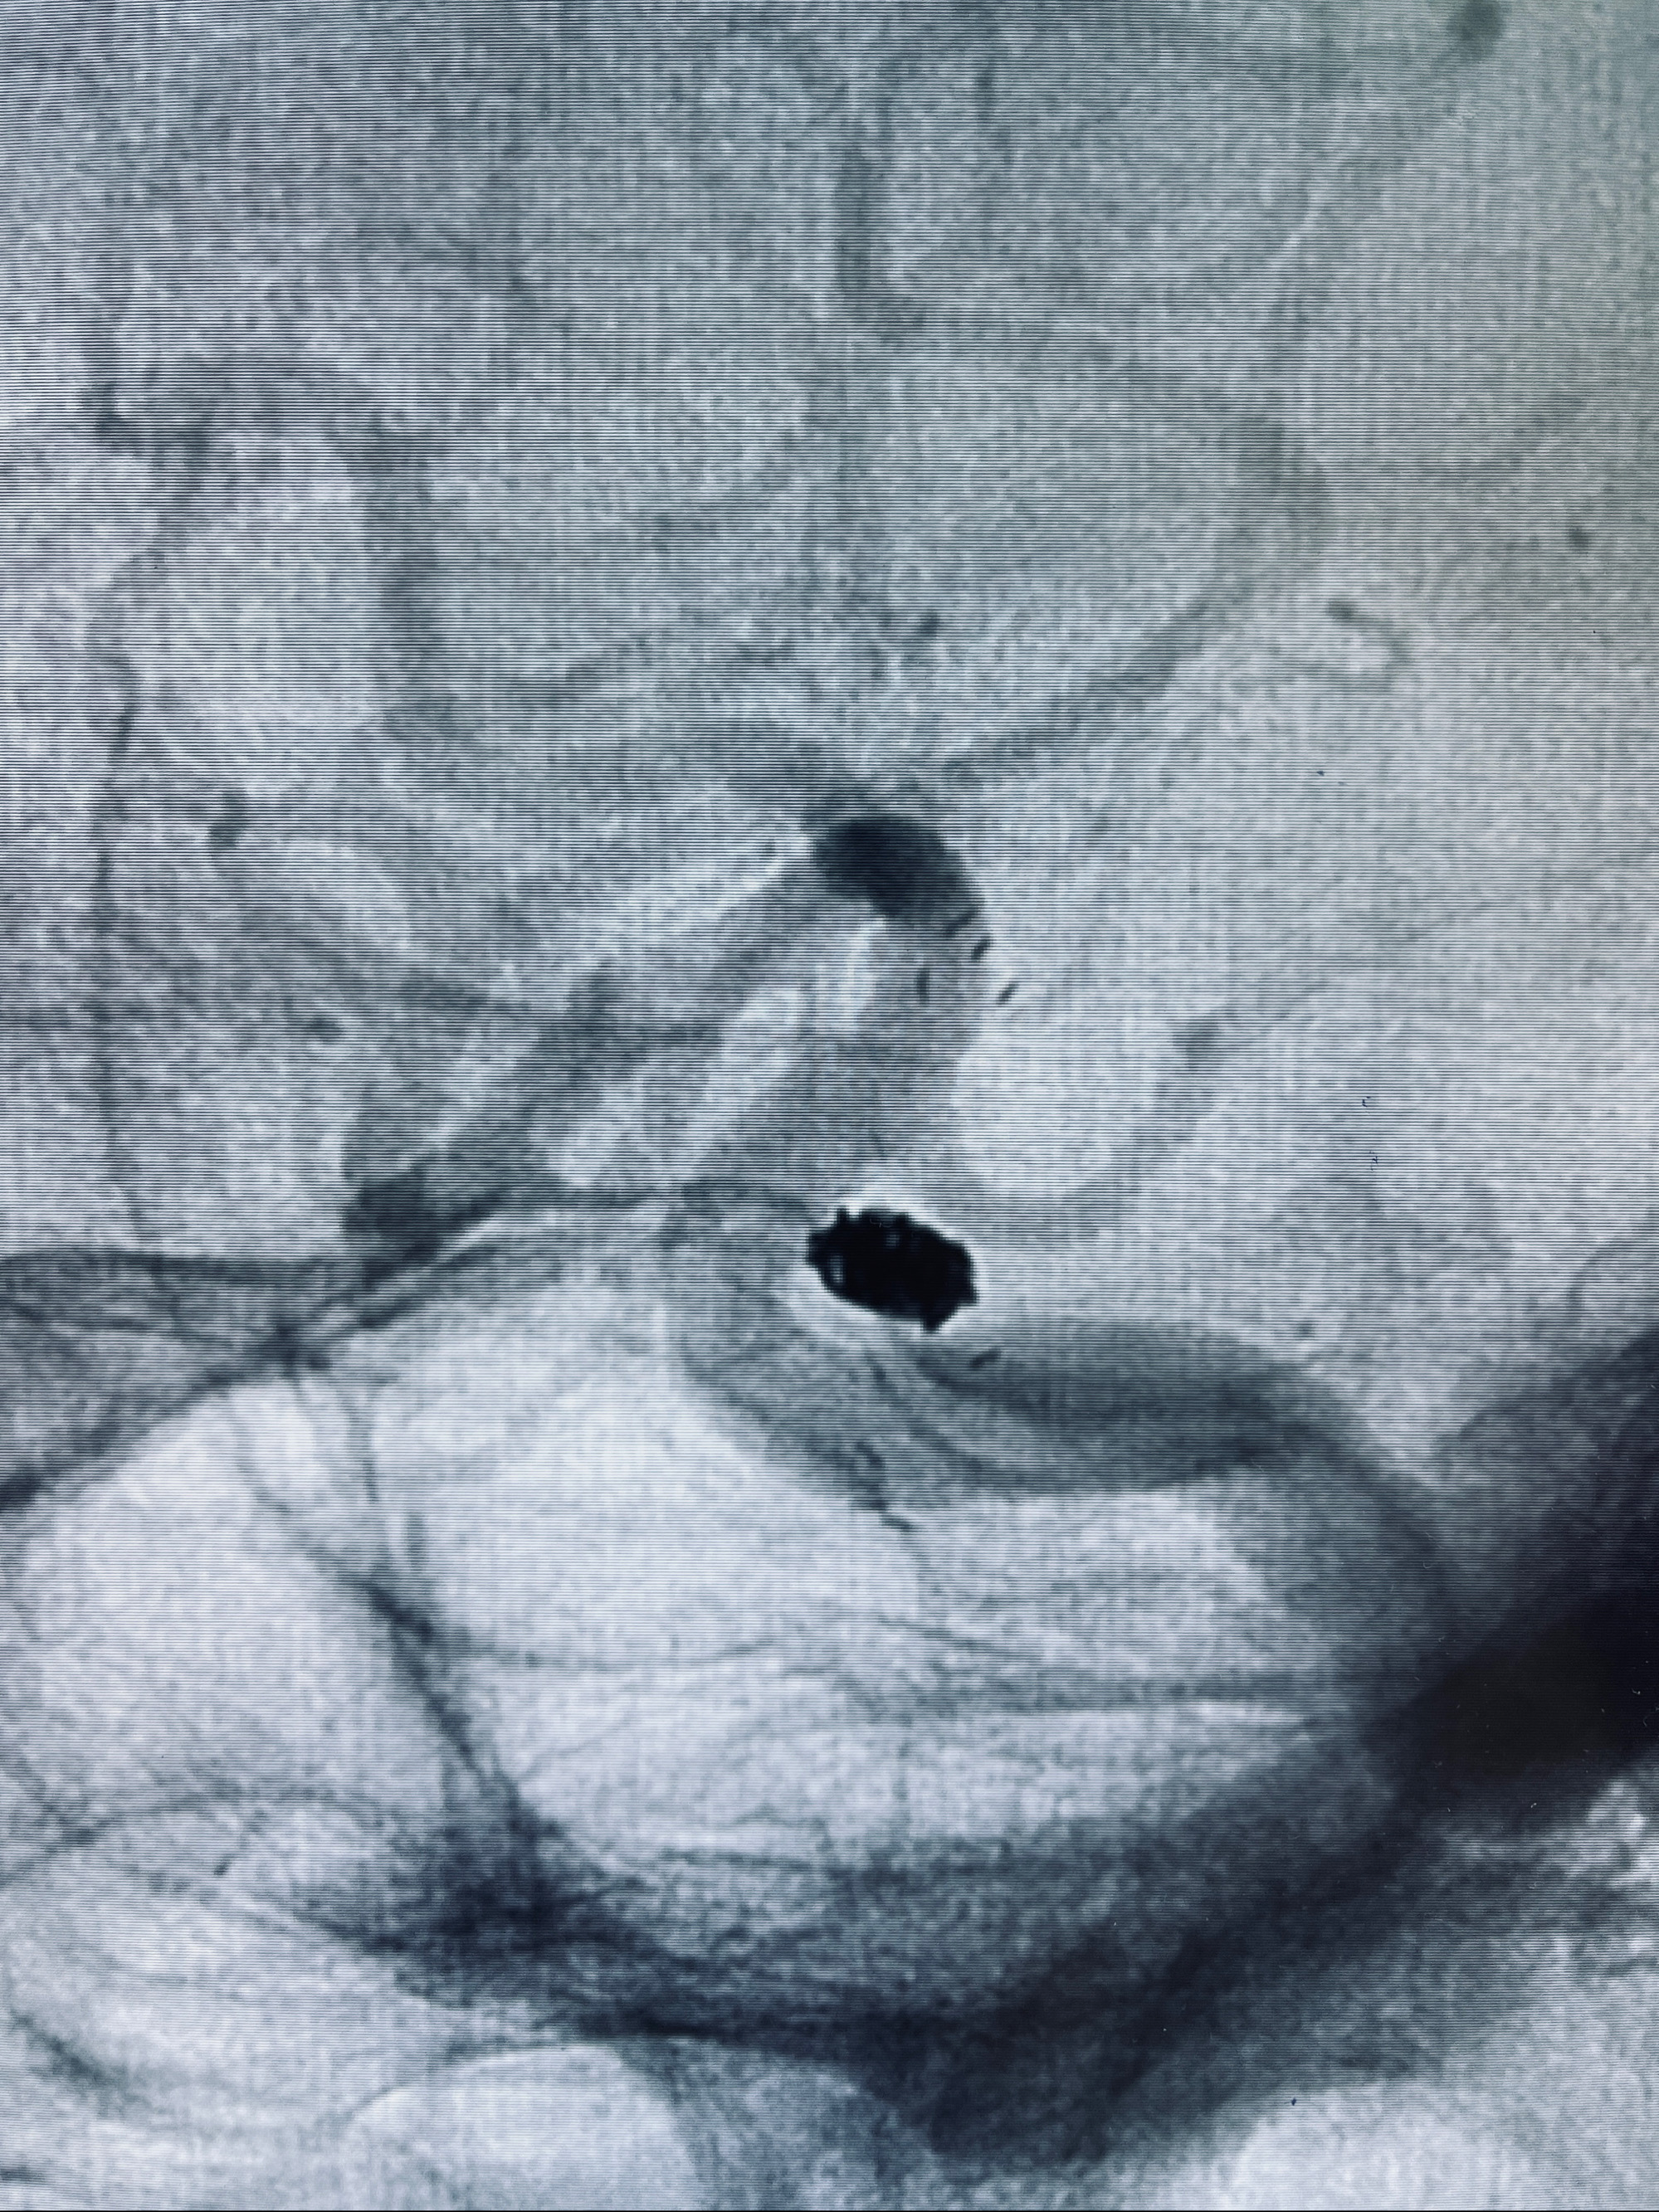

2022-09-29复查DSA

患者支架内血栓,给予阿司匹林+立普妥+依折麦布强化降脂干预